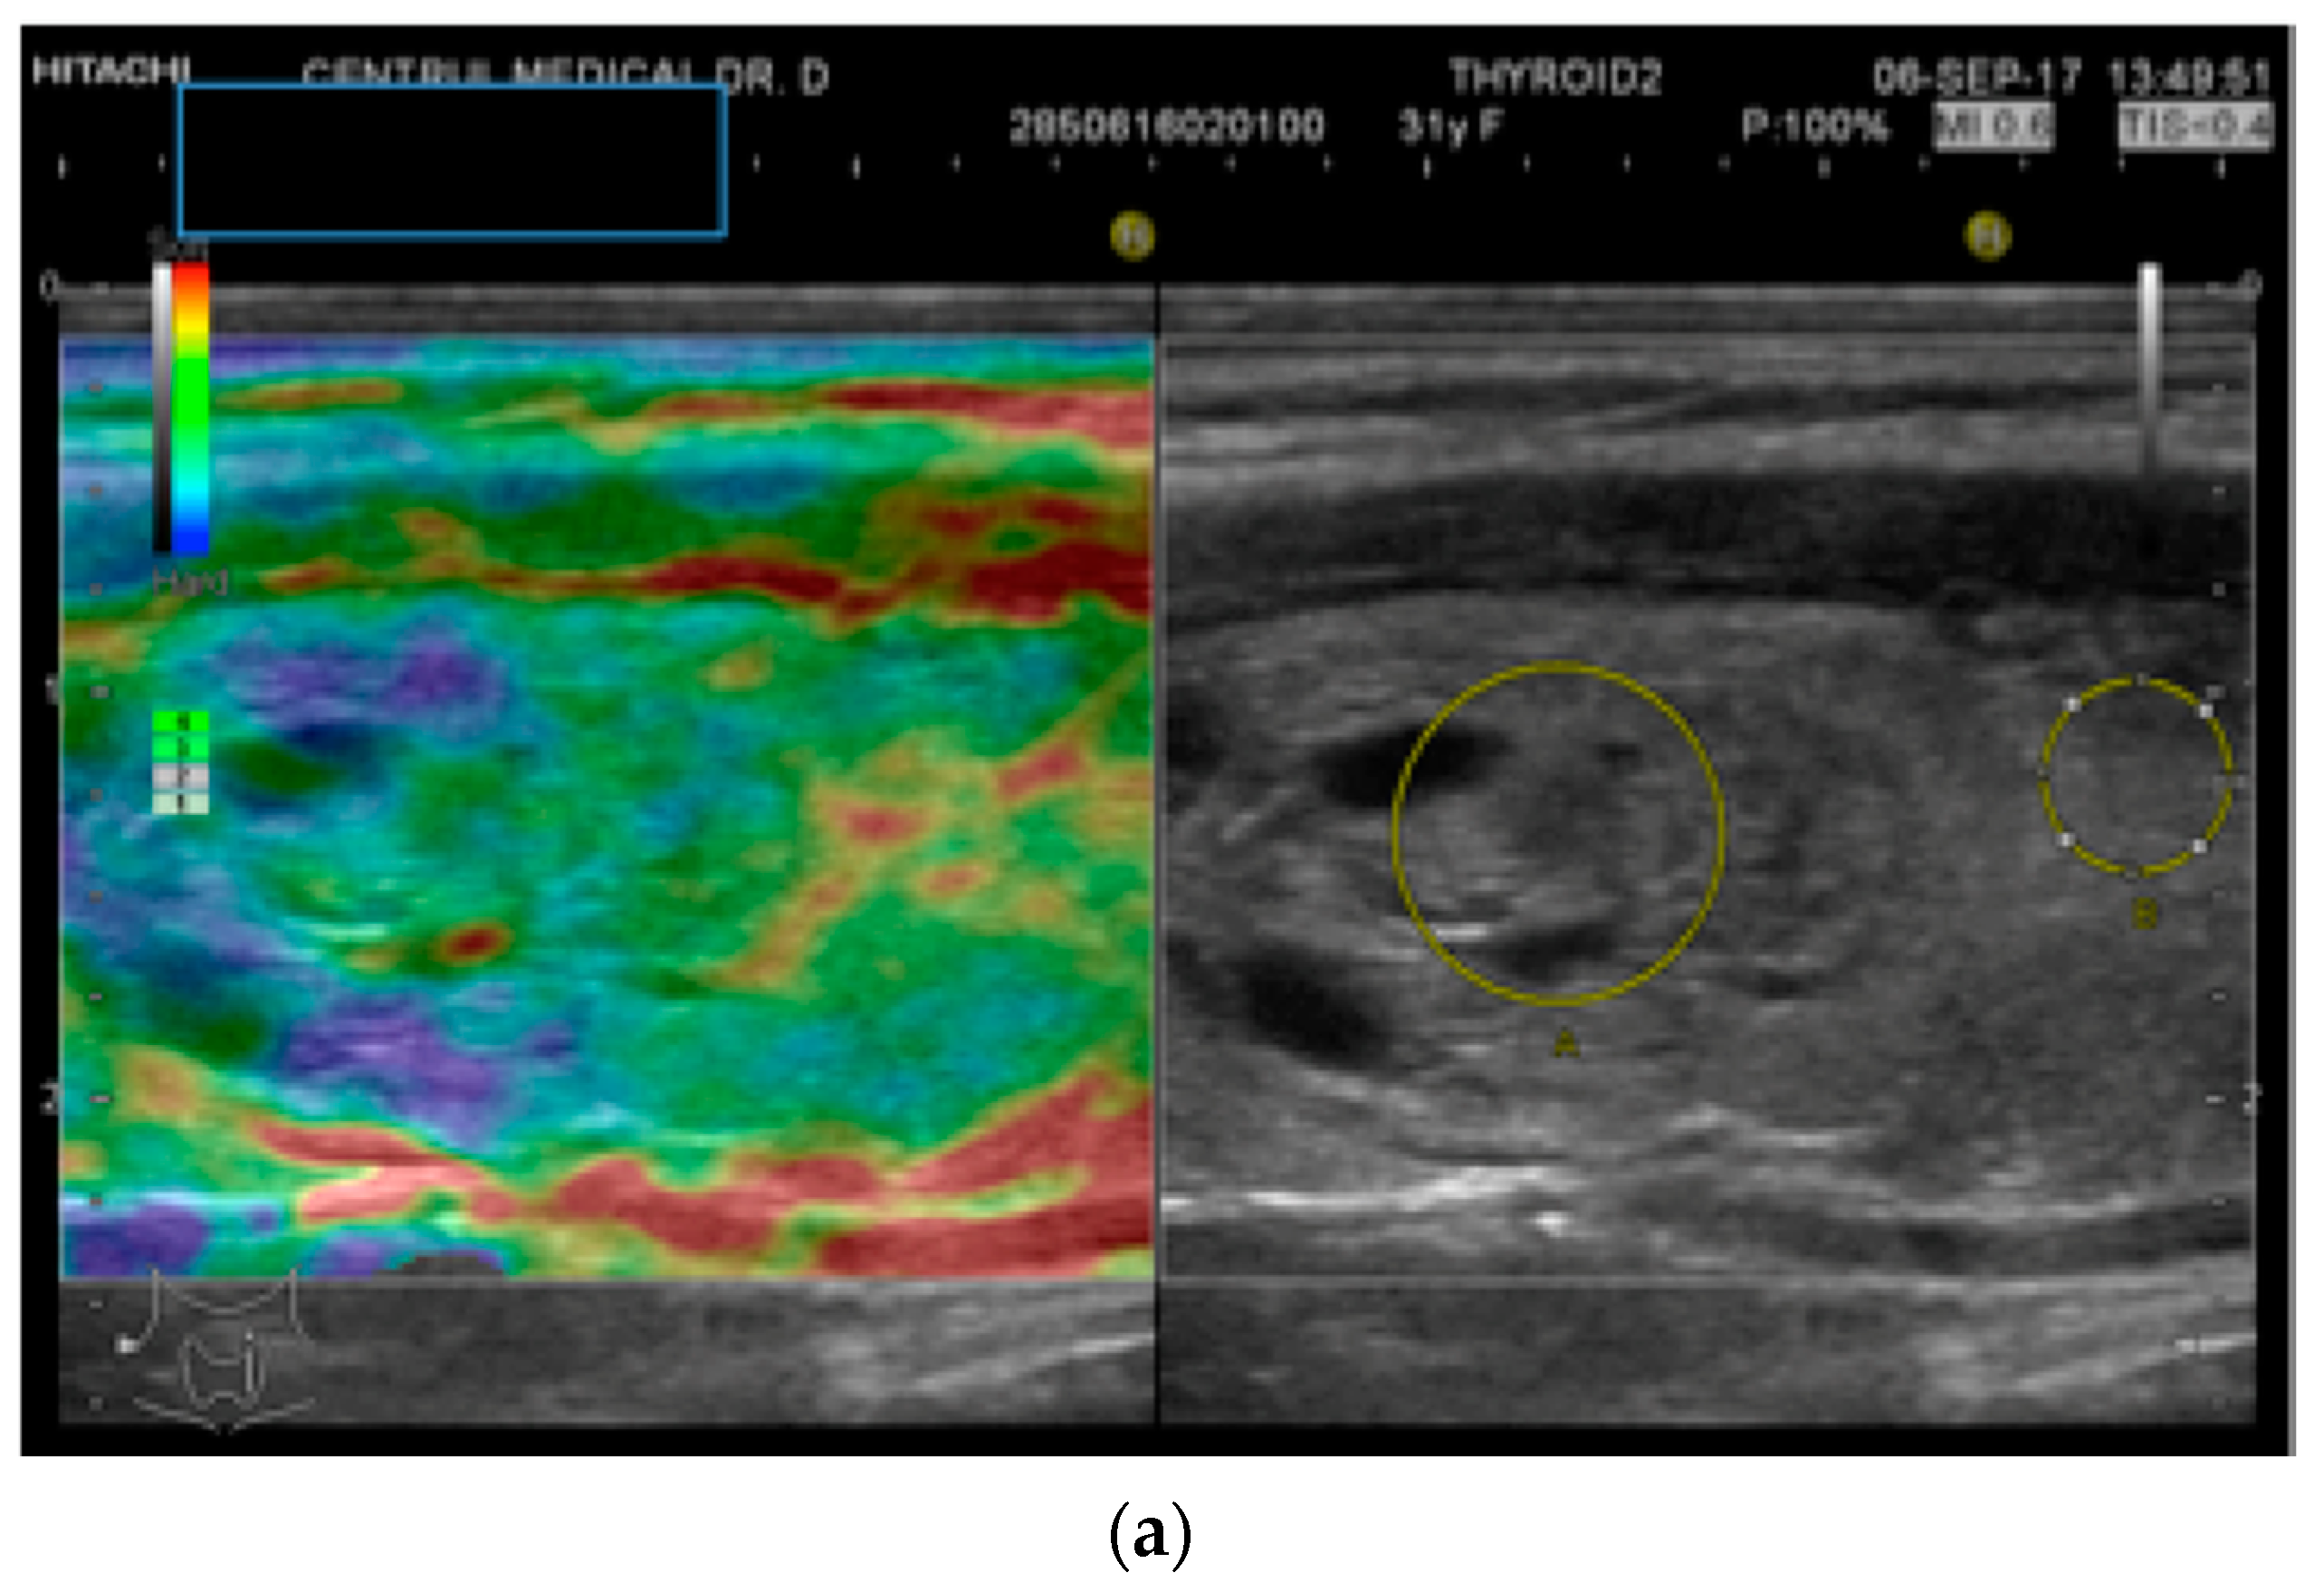

2.2. Elastography Measurements

- Stoian, D.; Timar, B.; Derban, M.; Pantea, S.; Varcus, F.; Craina, M.; Craciunescu, M. Thyroid Imaging Reporting and Data System (TI-RADS): The impact of quantitative strain elastography for better stratification of cancer risks. Med. Ultrason. 2015, 17, 327–332. [Google Scholar] [CrossRef]

- Stoian, D.; Borcan, F.; Petre, I.; Mozos, I.; Varcus, F.; Ivan, V.; Cioca, A.; Apostol, A.; Dehelean, C.A. Strain elastography as a valuable diagnosis tool in intermediate cytology (Bethesda III) thyroid nodules. Diagnostics 2019, 9, 119. [Google Scholar] [CrossRef]